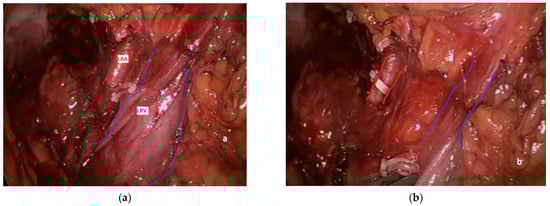

3. Extrarenal Visceral Arterial Injuries during Left Nephrectomy

3.3. Pathogenesis, Prevention and Diagnosis